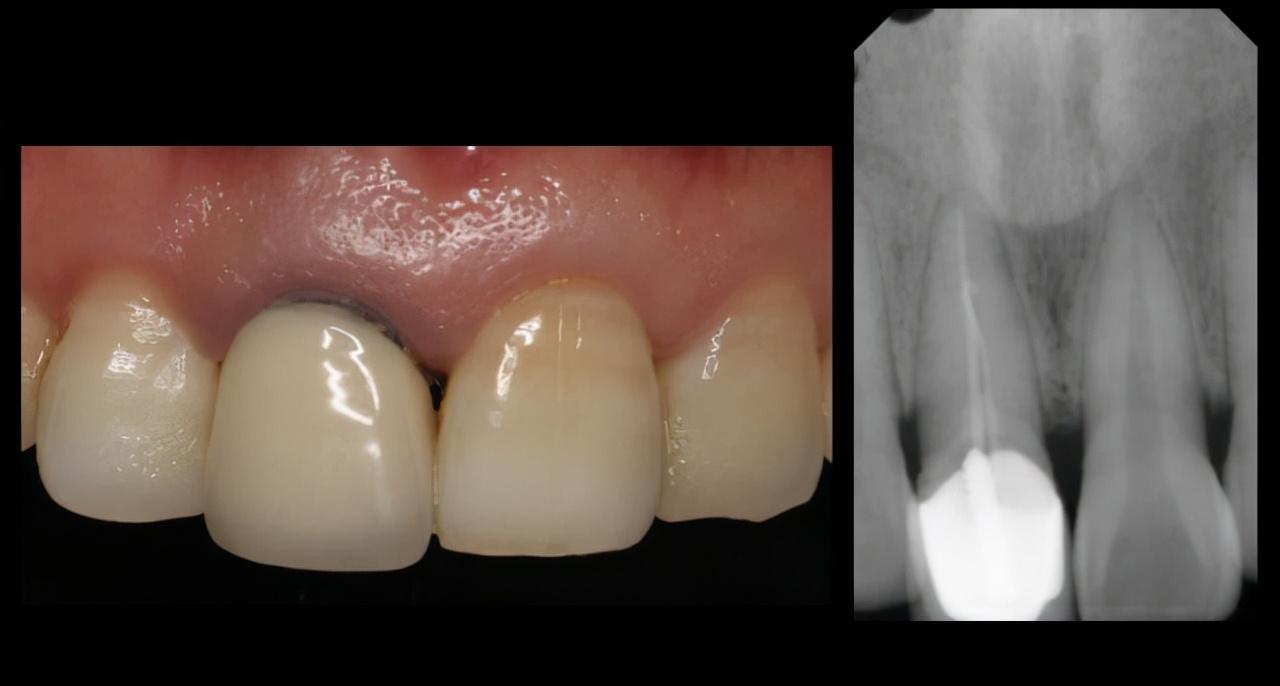

“幸好遇到了诊所的医生,不然那颗牙用纸包着到医院也救不回来了 。”看着走开的邻居,我突然想起之前遇到的一个小姑娘,也是八九岁的年纪,她是从滑梯上摔下来把门牙磕断的,被我的同事遇到就带回我们医院。从牙齿的保管到后面院内的紧急处理都很顺利,医生跟家长解释了“断牙再接”这项操作。但是她妈妈对于“断牙再接”持怀疑态度,打电话联系了开诊所的“亲戚”后,亲戚告诉她,断了就断了,等孩子再大一点补一下就好了。然后她就把孩子带走了。

不良修复体